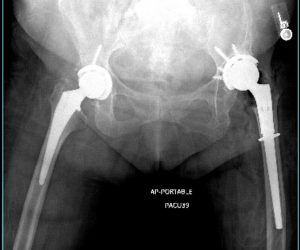

Knee Replacement